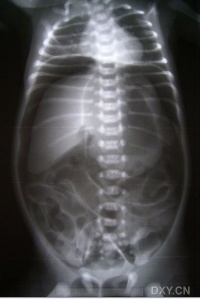

胃肠道穿孔的主要X线表现是气腹即腹膜腔内出现游离气体。关于气腹的显示方法,一般是采用透视与照片检查。尤其是少量气腹的显示则尤为重要,如病情允许,立

位透视并转动体位观察,此时往往能显示膈下新月形的游离气体的存在,因为气体总是具有浮游到腹腔最高处去的倾向,确定了膈下游离气体后,应即时照片以供临床参考。

在病情危重而不能坐或站立时,可采用仰卧侧位投照,此时气体可上升至前腹侧壁,可以见到腹壁与肝和肠之间有气层,使肝前下缘和肠外壁显示。

如情况只允许照仰卧位片时,只要能详细地认真阅片,亦可能发现有价值的征象:

一是见到明确的腹腔内脏器(胃肠和肝脾)的外壁;

二是腹腔内某些韧带(如肝脏前力的镰状韧带)的明确显示。见到这些征象

应考虑有气腹存在。如无气腹发现而临床又高度提示有急性胃肠道穿孔时,必要时可经胃管抽吸胃液后注入空气约300ml,则空气可从穿孔处逸出形成膈下游离气体,有助了胃、十二指肠溃疡穿孔的诊断。

胃肠道穿孔的传统诊断方法为摄取腹部X线平片,观察膈下、腹壁下有无游离气

体,以此作为主要诊断依据,但是准确性有限。